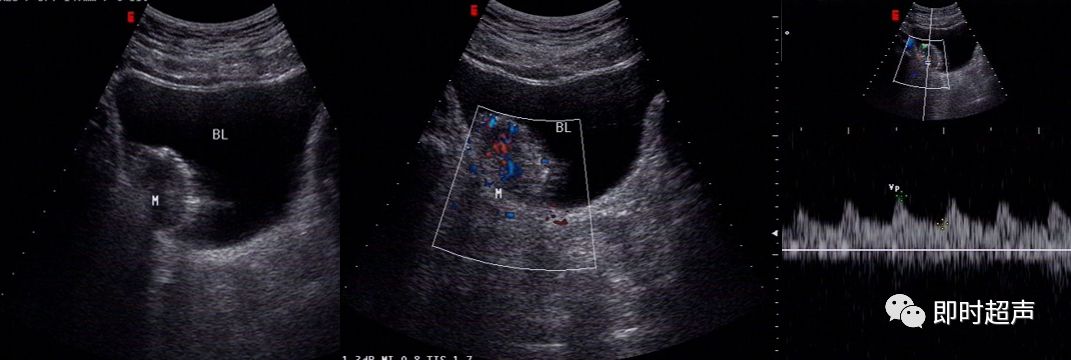

患者,男性,55岁,无痛肉眼血尿,临床实验室检查:尿常规:镜下血尿,超声声像图如下:

图1为二维声像图,肿瘤为稍强回声光团,呈不规则菜花样。

图2为彩色多普勒声像图,显示肿瘤内部可见细条状血流信号。

图3为彩色血流频谱图,显示肿瘤内部可见动脉频谱,RI=0.64。

诊断思路:

- 该患者为中年男性,为膀胱癌好发年龄

- 超声图像显示膀胱内可见一不规则菜花样团状中等回声

- CDFI:显示肿瘤基底部有细条状血流彩色Doppler频谱显示有动脉频谱:RI=0.64

- 综上所述,诊断应首先考虑膀胱恶性肿瘤

病理结果:

患者进行了肿块的切除,术后病理:膀胱移行上皮细胞腺癌